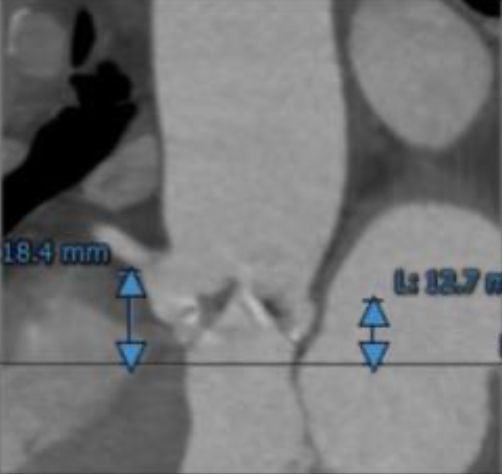

Type 1型二叶式主动脉瓣,瓣叶严重增厚,左右冠窦融合并形成钙化嵴,中度钙化,钙 化分布不均匀,最严重处为左右瓣叶融合嵴。主动脉瓣瓣环周长76.8mm,平均周长径24.3mm。

瓣环上钙化分布及主动脉解剖

该患者瓣叶中度钙化,左右瓣叶钙化融合嵴较为坚硬,球囊打开难度较高,预估存在植入假体瓣膜形变、根部损伤风险,钙化融合嵴增加瓣周漏风险。同时瓣叶严重纤维增厚,存在人工瓣膜向下位移,有瓣中瓣治疗可能。冠脉高度可,根据瓣叶长度、瓦氏窦宽度预估右冠风险较小,左冠存在一定堵塞风险。